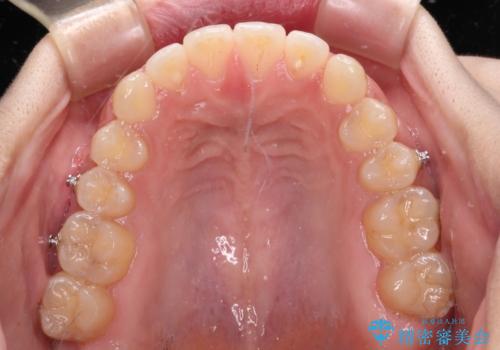

仕上がりとしては、もう少し上下前歯を接触させたかったのですが、ここまで改善されたことで患者様は大変満足され、治療を終えることとなりました。